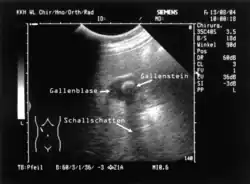

Sonografie einer Gallenblase mit einem einzelnen, ca. 1,3 Zentimeter großen Gallenstein.

• Ultraschalluntersuchung (Sonografie): Gallensteine und auch Entzündungen der Gallenblase lassen sich sonografisch gut darstellen. Kleine Cholesterinsteine, die den Gallengang verstopfen können, werden jedoch mitunter nicht gefunden.